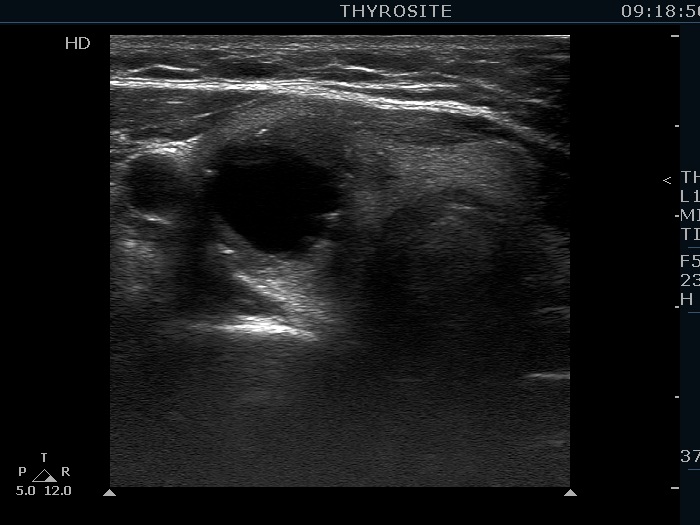

Benign hyperplastic nodule (histological diagnosis) - case 80

There were multiple foci of coarse calcification in this case. Note that acoustic shadowing is complete only at the edges of the lesions.